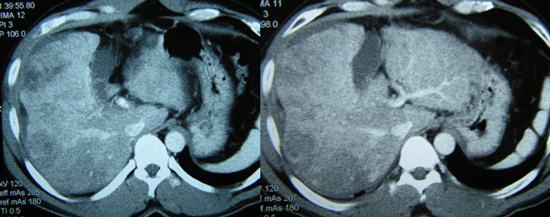

CT scan dibagian perut menunjukkan ada beberapa massa berukuran 7,3 x 5,1 cm ; 6,3 x 6,1 cm dan 7,3 x 4,5 cm, pada lobus kanan hati nya, dan diduga kanker hati yang telah menyebar atau metastasis kanker hati. Biopsi dilakukan pada tanggal 23 Desember 2010 dan dikonfirmasi sebagai kanker liver dengan sifat moderately differentiated.